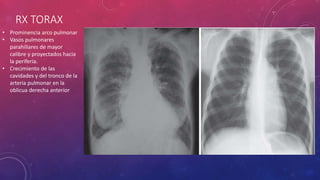

RX TORAX

• Prominencia arco pulmonar

• Vasos pulmonares

parahiliares de mayor

calibre y proyectados hacia

la periferia.

• Crecimiento de las

cavidades y del tronco de la

arteria pulmonar en la

oblicua derecha anterior